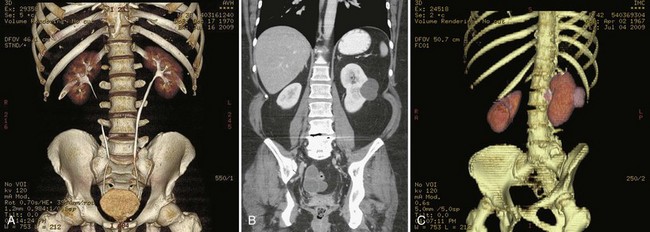

Three-dimensional (3-D) scanning has been used extensively in obstetrics and gynecology but so far has limited application in urology. 3-D scanning produces a composite of images (data set), which can then be manipulated to generate additional views of the anatomy in question (Fig. 4–28). 3-D rendering may be important in procedural planning and precise volumetric assessments (Ghani et al, 2008a, 2008b). 3-D scanning may allow the recognition of some tissue patterns that would otherwise be inapparent on two-dimensional scanning (Mitterberger et al, 2007b; Onik and Barzell, 2008).